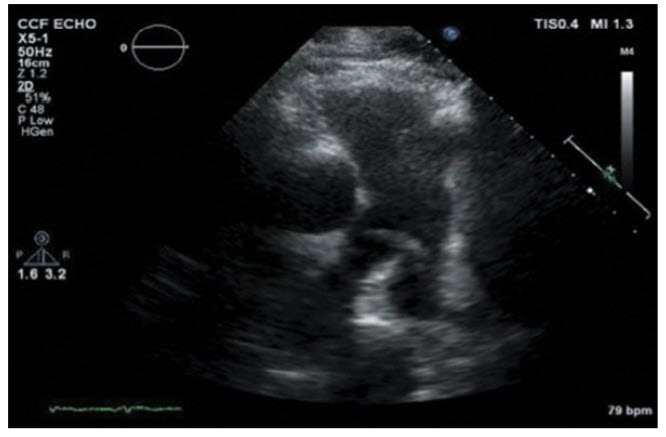

A 45-year-old man is status post hip replacement. He develops sudden-onset shortness of breath. On examination, he is hypotensive with a BP of 80/40 mmHg. An ECG shows sinus tachycardia at 100 beats per minute with ST elevation in V1 to V2 . A bedside echo is performed (Fig. below).

Initiate intravenous heparin and assess the risks and benefits of fibrinolysis. The echo shows a linear density in the main PA extending into the left PA. Findings are most consistent with a hemodynamically significant pulmonary embolism. Starting intravenous heparin and assessment for fibrinolysis are urgently indicated.